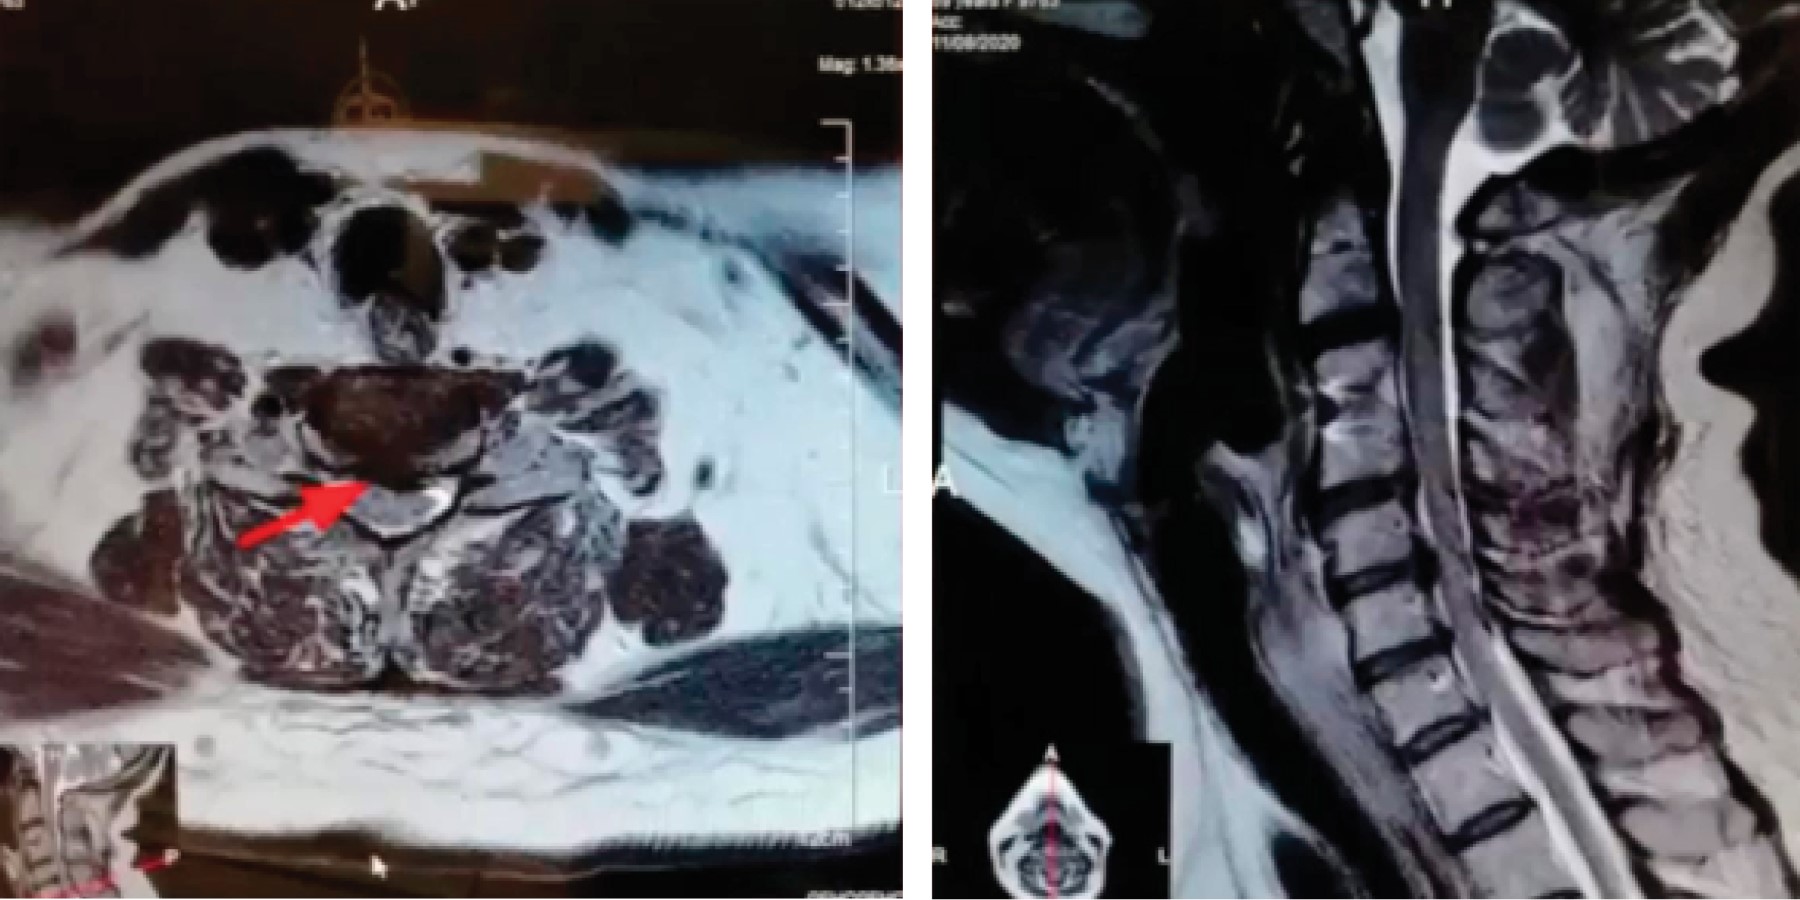

Figure 2